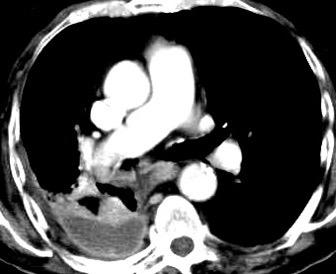

Signos radiológicos TC

Hallifax RJ et al. State-of-the-art: Radiological investigation of pleural disease Respiratory Medicine 2017

Nivel hidroaéreo o burbujas

Forma lenticular o elíptica Ángulos obtusos

> Grasa Extrapleural (60-80%)

Situación no gravitacional (no siempre)

Compresión de estructuras pulmonares

Límite muy bien definido Tabicación